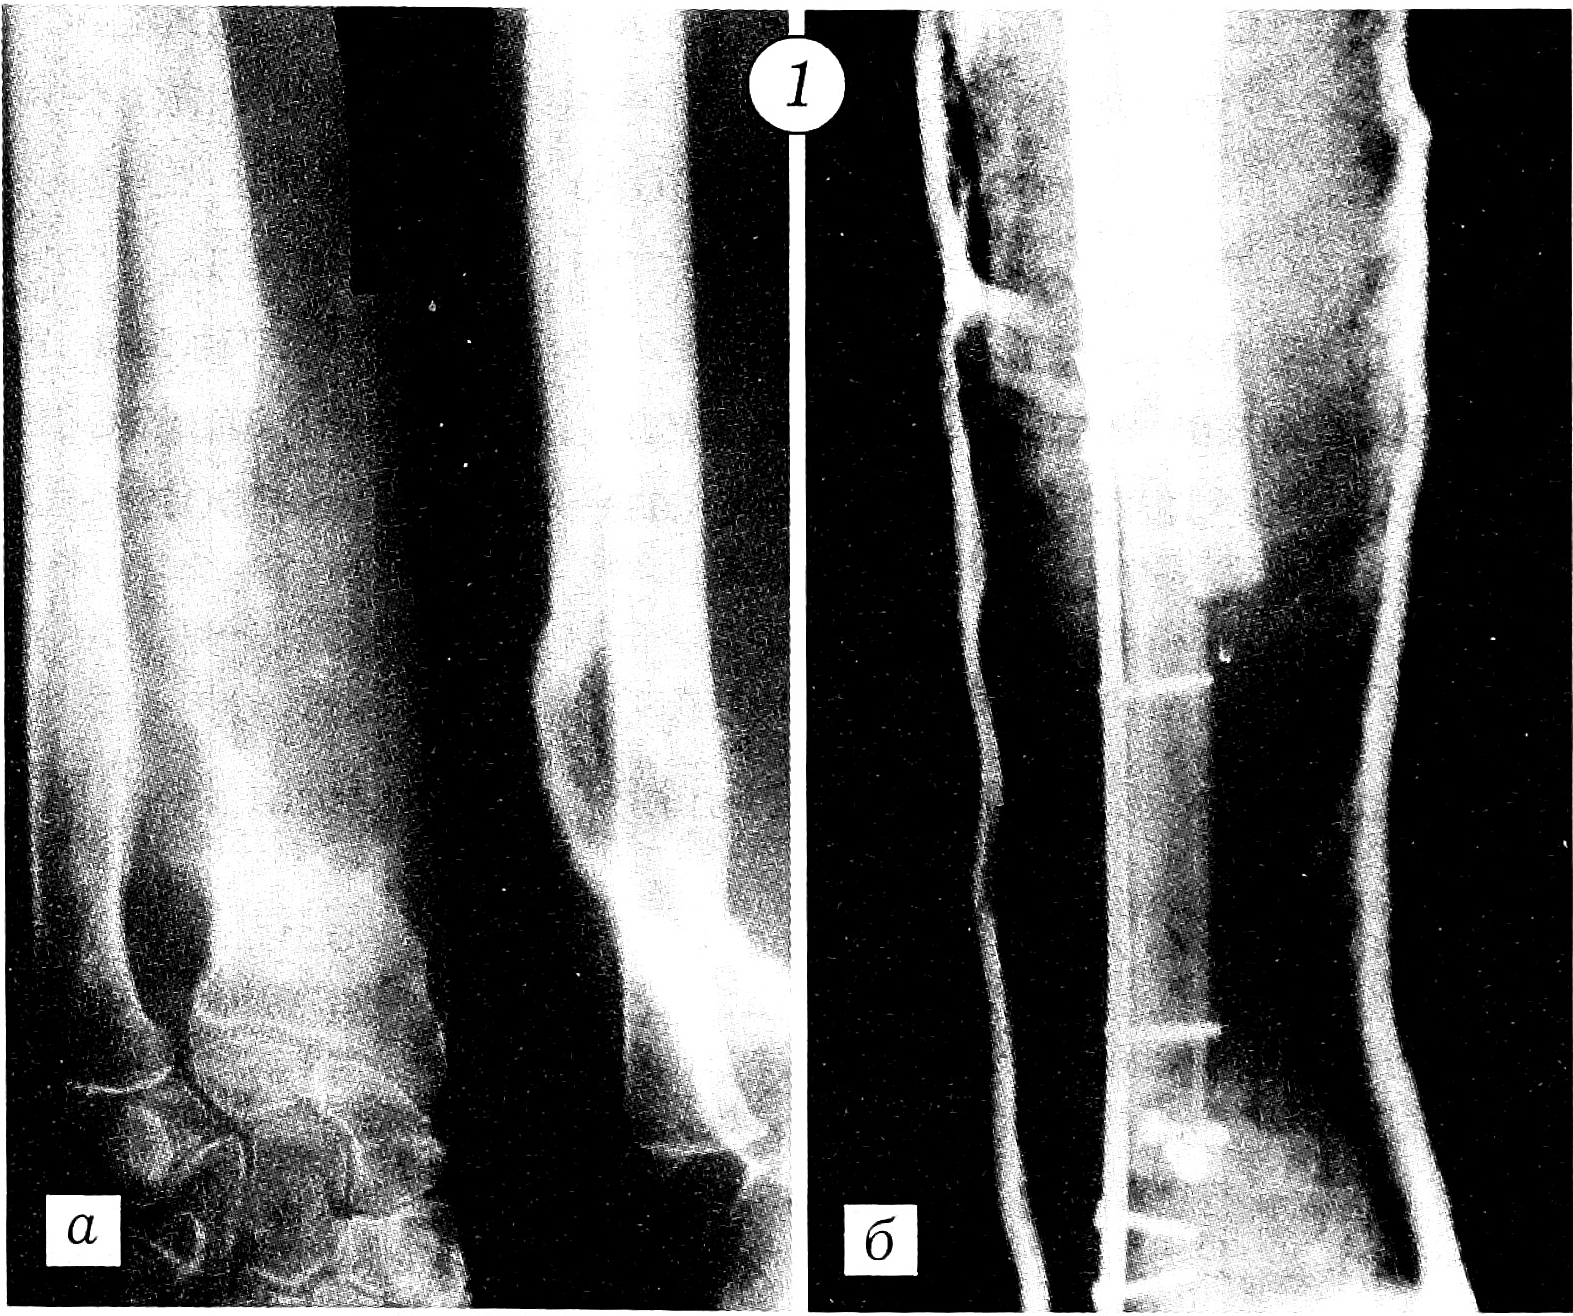

Фиксация отломков выполнялась по методике АО с применением металлоконструкций в комбинации с заполнением костного дефекта цементом [3, 5, 6]. Больной с обширным остеолитическим поражением проксимального отдела бедра произведено эндопротезирование. Поскольку ацетабулярный компонент тазобедренного сустава не был вовлечен в опухолевый процесс, выбран метод тотального эндопротезирования по Вирабову. Такая тактика снижает риск развития нестабильности сустава и необходимость повторных реконструктивных операций. При переломе диафиза плечевой кости отломки были фиксированы аппаратом Илизарова. У больного с патологическим переломом лучевой кости на фоне деструктивного остеолитического поражения, захватывающего ее дистальные 2/3, выполнена резекция патологического очага с последующим созданием синостоза культей лучевой кости с локтевой костью и артродезированием кистевого сустава длинной компрессионной пластиной АО (рис. 1). Больной с патологическим переломом головки и шейки плечевой кости после радикальной резекции метастатического остеолитического очага произведено эндопротезирование проксимального отдела плеча протезом из акрилоксида по Воронцову (рис. 2). При подвертельном переломе и переломах диафиза и шейки бедра после радикального удаления метастаза выполняли стабилизацию отломков Г-образными пластинами и конструкциями DHS с последующим заполнением образовавшегося дефекта костным цементом. В комбинации с компонентами стабилизирующих конструкций костный цемент повышает прочность фиксации (рис. 3 и 4).

Рис. 1. Рентгенограммы правого предплечья больного с переломом лучевой кости в области метастаза рака нижней губы. а — до операции; б — после операции.